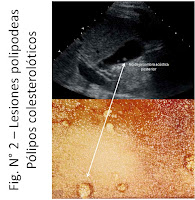

Figura N° 2

Un  ecografista entonces puede sugerir una lesión pediculada o de forma polipoidea, pero la ecografía no es exacta cuando se trata de definir el origen de la lesión. En términos epidemiológicos esto lo conocemos como alta sensibilidad pero baja especificidad, en este caso de la ecografía. Por ejemplo un ecografista podría sugerir de manera incorrecta un “pólipo vesicular” porque es una lesión al interior de la vesícula, pediculada o de forma polipoidea, que no deja sombra acústica posterior y no se moviliza al mover al paciente. Sin embargo cuando operamos al paciente encontramos que la lesión es un acúmulo de colesterol en las paredes vesiculares ("pólipo" colesterolótico). Esta lesión senso estricto no es un pólipo vesicular sino un acúmulo anormal de colesterol en las paredes internas de la vesícula (mucosa). En ese caso el diagnóstico ecográfico más certero sería lesión polipoidea vesicular, es decir la observación de una lesión que parece un pólipo vesicular. Más aún, dos terceras partes de las lesiones polipoideas vesiculares son de origen colesterolótico. Esto se puede apreciar en la Fig. N° 2 en donde el ecografista ve imágenes polipoideas en la vesícula biliar, sin sombra acústica posterior y el hallazgo son pólipos colesterolóticos.